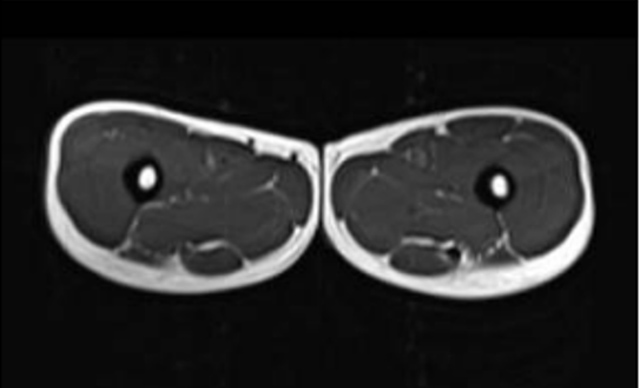

Vergleich des Oberschenkelquerschnitts eines 21-jährigen und eines 83-jährigen – weiss ist Fettgewebe

(Quelle:  published online on 01.11.2019, https://doi.org/10.34045/SSEM/2014/25)